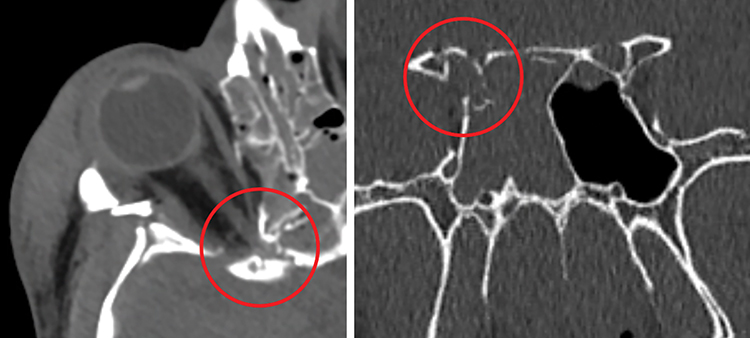

Bony impingement: A posterior direct TON that results from impingement of the apical or intracanalicular optic nerve from a fracture at the orbital apex and/or optic canal. Mechanisms vary widely. Direct bony impingement on the optic canal may result from a skull base fracture that also involves adjacent structures, including the cavernous sinus, with resultant cranial neuropathy (See Figure 3.21.1).

CT scan of the head and orbit (axial, coronal, and parasagittal views) with thin (i.e., 1-mm) sections through the optic canal and skull base to rule out an intraorbital foreign body or bony impingement on the optic nerve. There may be fractures along the cribriform plate, the sphenoid sinus, and the medial wall of the cavernous sinus. A normal CT in no way rules out posterior indirect TON. Similarly, an optic canal fracture does not mean TON is present.